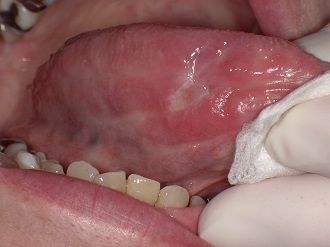

舌の裏に出来る水ぶくれ・粘液嚢胞とは久喜・いしはた歯科。

好きです: 446